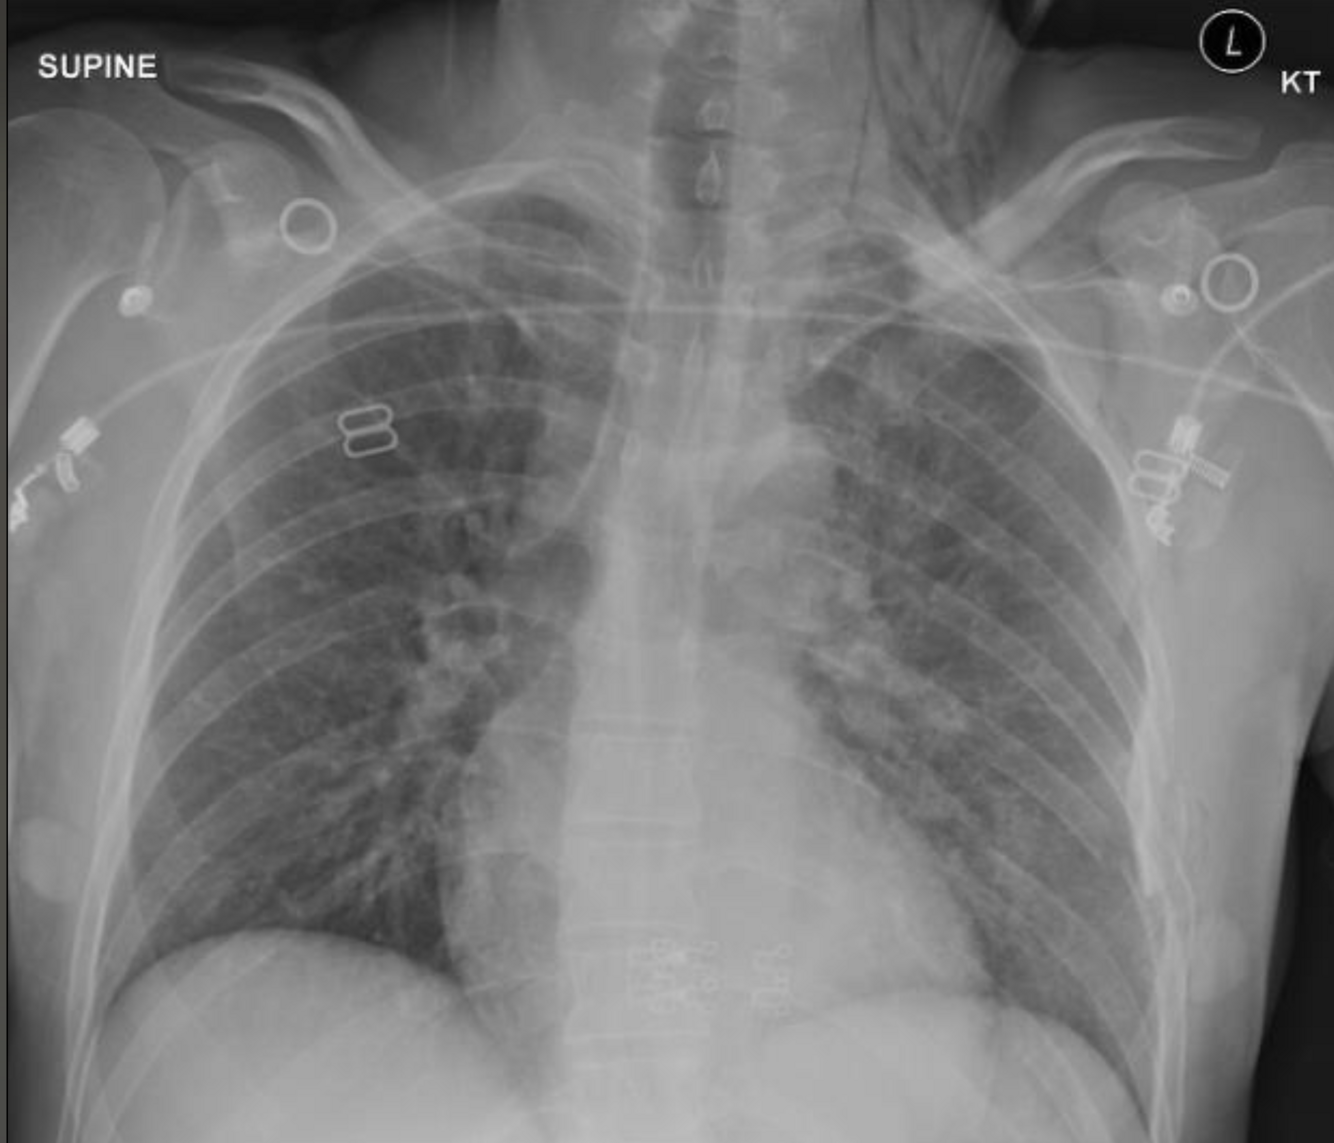

93

bilateral pneumothoracis right heamothroax deep sulcus sign right